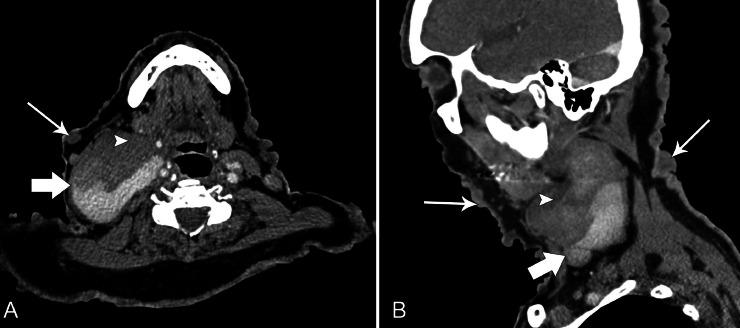

Neurofibromatosis Type 1 (NF1) is a rare autosomal dominant disorder that has a wide array of clinical manifestations. NF1 Vasculopathies constitute 0.4% to 6.4% of the findings and they often develop in the arterial circulation while venous involvement is rare. We present a case of a 73-year-old male with NF1 with an incidental finding of right neck swelling for 2 months. Different radiological modalities were performed, identifying the lesion as an internal jugular vein aneurysm. The patient was managed conservatively as he was asymptomatic in relation to the swelling. NF1 venous vasculopathies are rare but they have detrimental consequences such as rupture and severe hemorrhage in view of the fragility of the aneurysmal wall and the infiltration of the neurofibroma into the vessel. Hence, high clinical suspicion and selective imaging and follow-up is advisable for physicians.

1型神经纤维瘤病(NF1)是一种罕见的常染色体显性疾病,具有广泛的临床表现。NF1血管病变占所有检查结果的0.4%至6.4%,常发生于动脉循环,而静脉受累罕见。我们报告一例73岁男性NF1患者,偶然发现右颈部肿胀2个月。进行了不同的影像学检查,确定病变为颈内静脉动脉瘤。由于患者肿胀部位无症状,因此采取了保守治疗。鉴于动脉瘤壁的脆弱性以及神经纤维瘤向血管内浸润,NF1静脉血管病变虽罕见,但可导致破裂和严重出血等不良后果。因此,医生应保持高度临床怀疑,并进行选择性影像学检查和随访。